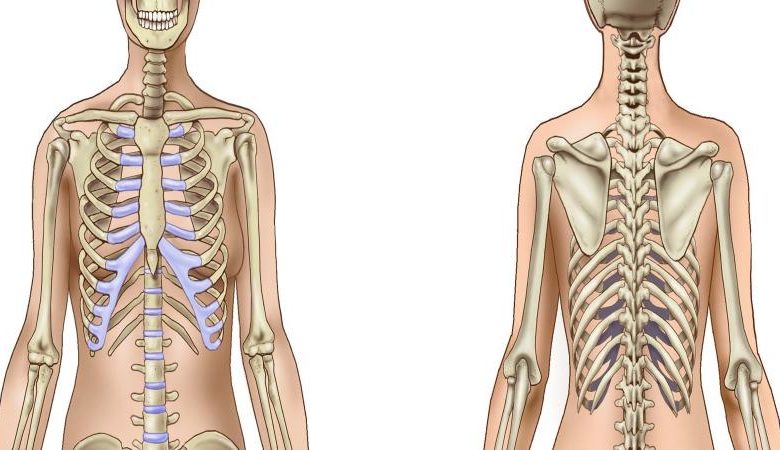

Çok basit hayvanlar dışında, canlıların çoğunda gövde yapısının temelini teşkil eden, ve bütün gövdenin ve ayrı ayrı parçalarının genel şekil ve büyüklüklerini tespit eden ve aynı zamanda gövde ve çeşitli organlar için destek görevini yapan bir İskelet vardır.

Çeşitli şekil ve büyüklükte olan 206 kemik, insan cinsi için belirli olan bir sıra ve sistem içinde birbirine bağlanmak suretiyle bütün gövde çeşitli organların desteğini yapan iskeleti meydana getirirler. iskelet, aynı zamanda gövde yapısının esasını teşkil eder ve yumuşak dokulardan yapılmış çeşitli organlar, bu esasa dayanmakta ve bütün organlar, ya doğrudan doğruya veya başka organlar aracılığı ile iskelet parçalarına bağlanmıştır. Çeşitli oynar eklemler aracılığı ile birbirine bağlı olan kemikler, çeşitli vücut parçalarımızı harekete geçirirken, kaldıraç görevini yaparlar. Bundan başka kafa ve göğüs boşluğu için boşlukları sınırlamak suretiyle, kemikler bu boşluklarda bulunan önemli organları dışarıdan gelebilecek etkilere karşı korunmasını sağlarlar. 60-70 kilo ağırlığında olan vücudumuz için destek, oldukça ağır gövde parçalarımızın hareketleri sırasında kaldıraç ve beyin, yürek ve akciğer gibi önemli organlarımız için koruma görevini yapabilmesi için kemiklerin, sert, sağlam ve dayanıklı dokudan yapılmış olması lazımdır. Kemiklerin ince yapısını inceleyecek olursak, dokunun görevi bakımından kemiklerde aranılan niteliklerin bulunduğunu görürüz.

İnsan iskeleti aksial ve appendiküler İskelet olmak üzere iki kısımdan meydana gelir. İnsan vücudunda toplam 206 kemik bulunmaktadır. Ancak bu sayı sabit değildir.yaşa göre değişiklik gösterebilir.

3.Yassı kemikler (ossa plana): Costalar, sternum, skapula ve kafatası kemikleri bu guruba girerler. Genellikle ince ve kıvrık bir tabaka halindedirler. Dış ve iç iki kompakt tabaka ile bunun arasında spongioz kemikten yapılmışlardır. Kemik iliği içerirler. Kafatası kemiklerindeki spongioz tabakaya özel olarak -diploe- denir. Diploe içinde bir çok ven kanalcıkları vardır. Bazı yassı kemikler (lacrimal) yalnızca bir kompakt kemik yaprağından ibarettir. Eklem yüzleri kıkırdak veya fıbrözdoku ile kaplıdır.